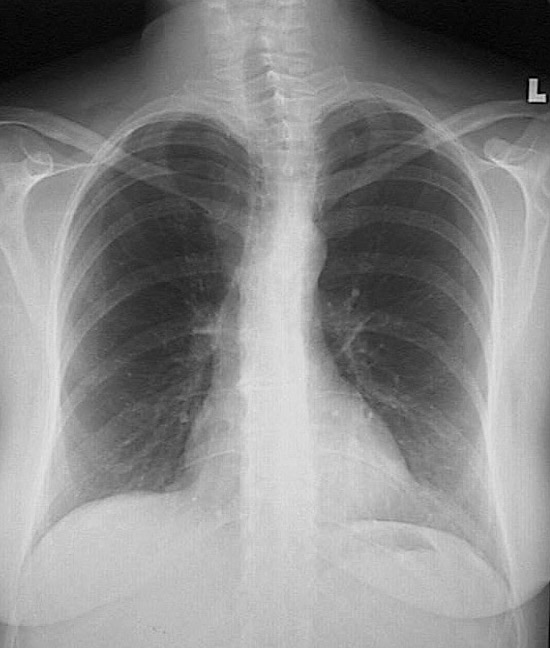

This is a normal PA chest radiograph in a female who has slight upper thoracic spondylosis with scoliosis. The lower margins of the right and left breasts are apparent.